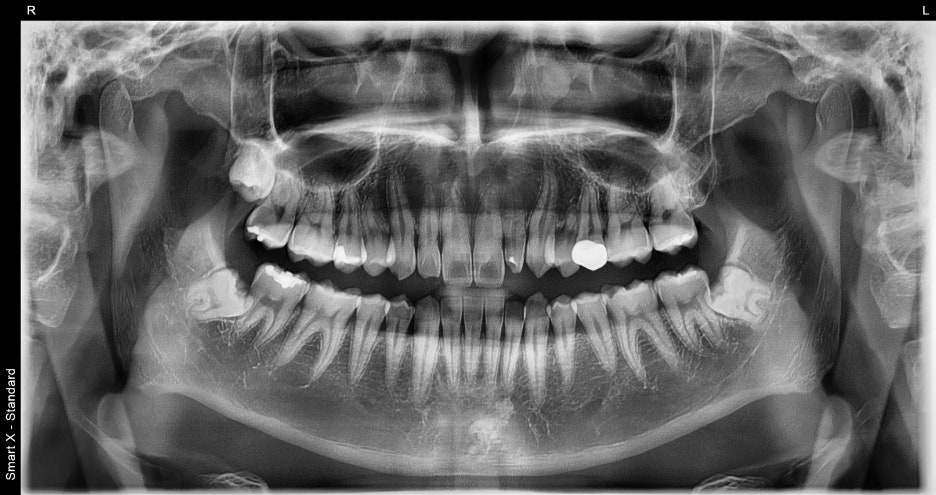

환자분의 초기상태

-왜 오브제로가 필요한 상황이었을까?

처음 내원 당시 환자분은

오브제로 라미네이트

1.앞니 옆 치아가 작게 나 있는 형태

2.레진 변색

3.전체적으로 어둡게 보이는 치아 색

이 세 가지 문제로 고민하고 있었습니다.